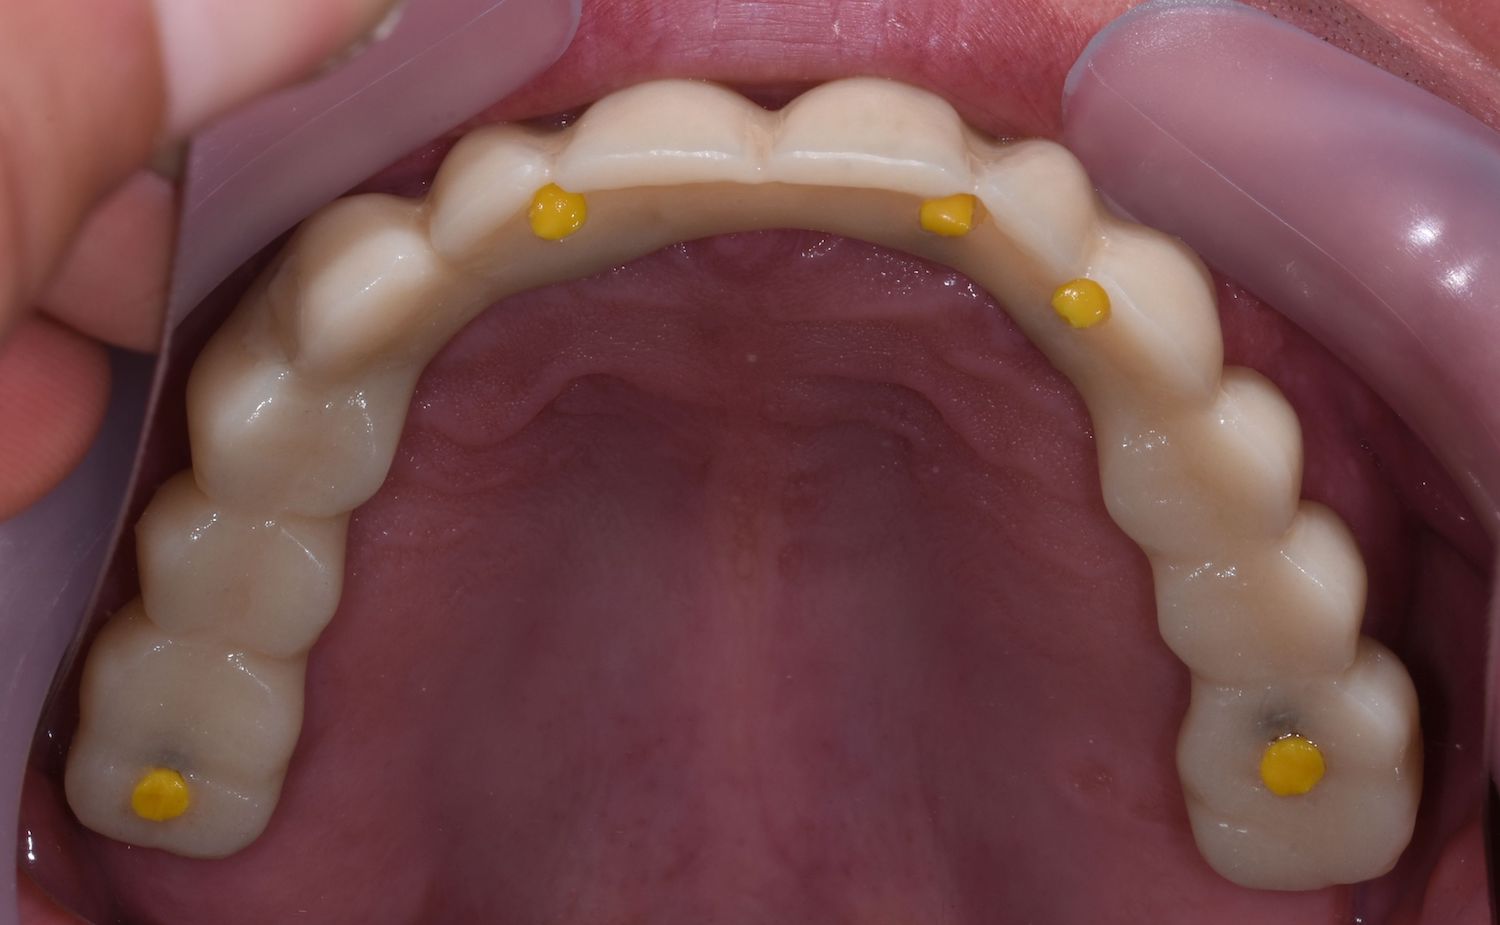

2. Zkouška tvaru a přesnosti v definitivním anatomickém tvaru pomocí bílého resinu nebo frézovaného či tištěného PMMA ✅

Po odsouhlasení přesného dosedu, správného tvaru a skusu zhotovujeme definitivní zubní náhradu 👇

Zkouška přesnosti a tvaru pomocí PMMA

Pomocí PMMA je konečný výsledek Branemarku kompletně předem vyzkoušený a odsouhlasený lékařem i pacientem.

Při odevzdávání tedy nehrozí žádné překvapení.